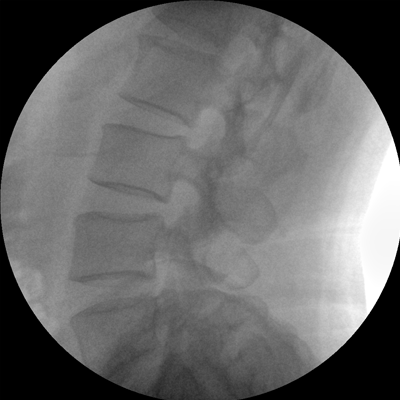

Clinical picture

臨床圖片